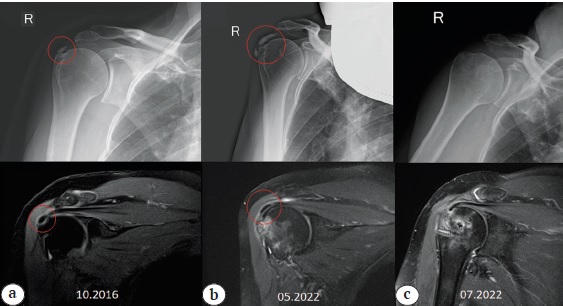

Fig. 4. Case 2. Dynamics of the increase in calcification of the rotator cuff according to X-ray and MRI in the PD mode: a — at the initial visit (calcification of the supraspinatus tendon); b, c — increase in calcification; d — X-ray of the shoulder joint after removal of the calcium deposit. Red circle — location of the calcification